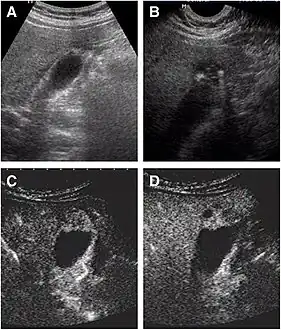

Abdominal ultrasound has low accuracy in differentiating gall bladder adenomyomatosis from cancer and is operator dependent. However, it is used as the exam of the first-line due to its wide availability. Ultrasound findings may show thickened gall bladder wall, tiny anechoic spaces (Rokitansky–Aschoff sinuses or RAS), and twinkling artifact (or comet-tail reverberation). Comet tail reverberation, which is due to reflections from cholesterol crystals, is a highly specific sign for adenomyomatosis.[9]

8. Tang S, Huang L, Wang Y, Wang Y (August 2015). "Contrast-enhanced ultrasonography diagnosis of fundal localized type of gallbladder adenomyomatosis". BMC Gastroenterology. 15 (1): 99. doi:10.1186/s12876-015-0326-y. PMC 4524444. PMID 26239485.{{cite journal}}: CS1 maint: unflagged free DOI (link)